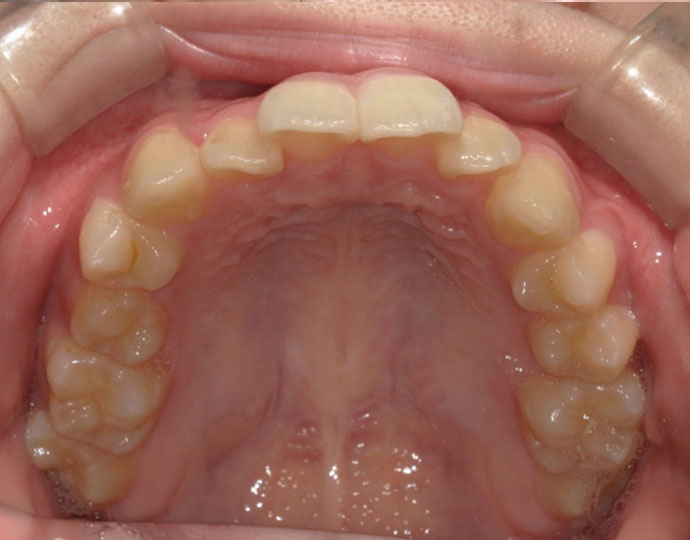

治療前

| 患者様 | 女性 18歳 |

| 主訴 | 歯並びを綺麗にしたい。 |

| 診断 | 叢生歯列不正咬合 |

| 治療方針 | 上下顎左右第一小臼歯の抜歯(計4歯) |

| 治療に使用した装置 | セルフライゲーションブラケット(インタラクティブタイプ) |

| 治療期間 | 2年2カ月 |

| 治療回数 | 24回 |

| 治療費(自費診療) | 847,000円(税込み) |